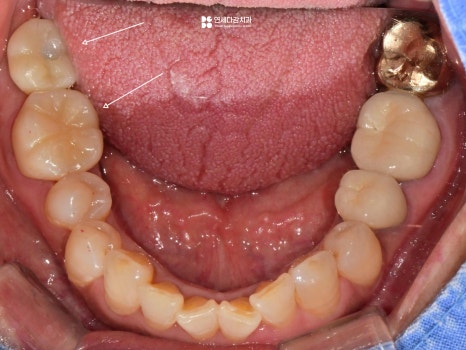

2026.02.13

이렇게 식립된 임플란트도 유착 기간을 거쳐

보철을 수복하면 마무리가 됩니다.

각각 부위마다 염증 소견은 없는 것으로 봐서,

상태는 양호한 것으로 평가됩니다.

진료 후에도 정기적인 확인을 통해

이상 소견이 없는지 꾸준히 살펴보는 것이

치아를 오래 유지하는 데 중요합니다.